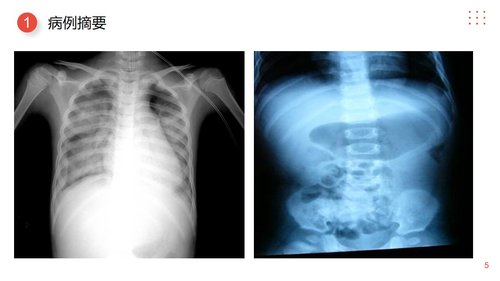

本PPT文档系统阐述了一例小儿肠套叠病例的护理查房全过程,核心内容围绕一名3个月大男婴(王XX)因阵发性哭闹、呕吐及血便入院,经诊断为肠套叠并行“肠切除肠吻合术+阑尾切除术”后的围手术期护理。文档结构清晰,依次涵盖病例摘要、护理评估、诊断、目标、措施及评价。病例摘要部分详细列出了患儿的基本信息、阳性体征(如左下腹质硬包块)、主要检验结果(提示低蛋白、贫血、电解质紊乱等)以及治疗原则。护理评估从健康史、身体状况、辅助检查及家族史多维度分析了患儿的整体状况。基于评估,文档明确了核心护理问题,并设定了明确的预期目标,包括维持呼吸道通畅、确保管道安全、维持水电解质平衡、保护皮肤完整性及预防切口感染等。为实现这些目标,文档重点详述了具体、可操作的护理措施:在预防窒息方面,强调保持呼吸道通畅;在管道护理上,要求妥善固定并密切观察胃肠减压管、尿管及肛管;在营养支持方面,规划了静脉营养方案并强调输液管理;在皮肤护理上,注重保持清洁干燥;同时,还包含了对疼痛管理及潜在并发症(如腹痛、腹胀、感染)的监测与应对。最后,护理评价部分显示,通过上述综合护理干预,所有预设目标均得以实现,患儿未发生窒息、管道脱出、皮肤破损、切口…